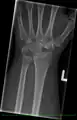

Negative ulnar variance.

Some Kienböck's patients present with an abnormally large difference in length between the radius and the ulna, termed "ulnar variance", which is hypothesized to cause undue pressure on the lunate, contributing to its avascularity. In cases with such a difference, radial shortening is commonly performed. In this procedure, the radius (the lateral long bone) is shortened by a given length, usually between 2 and 5 mm, to relieve the pressure on the dying lunate. A titanium plate is inserted to hold the newly shortened bone together.